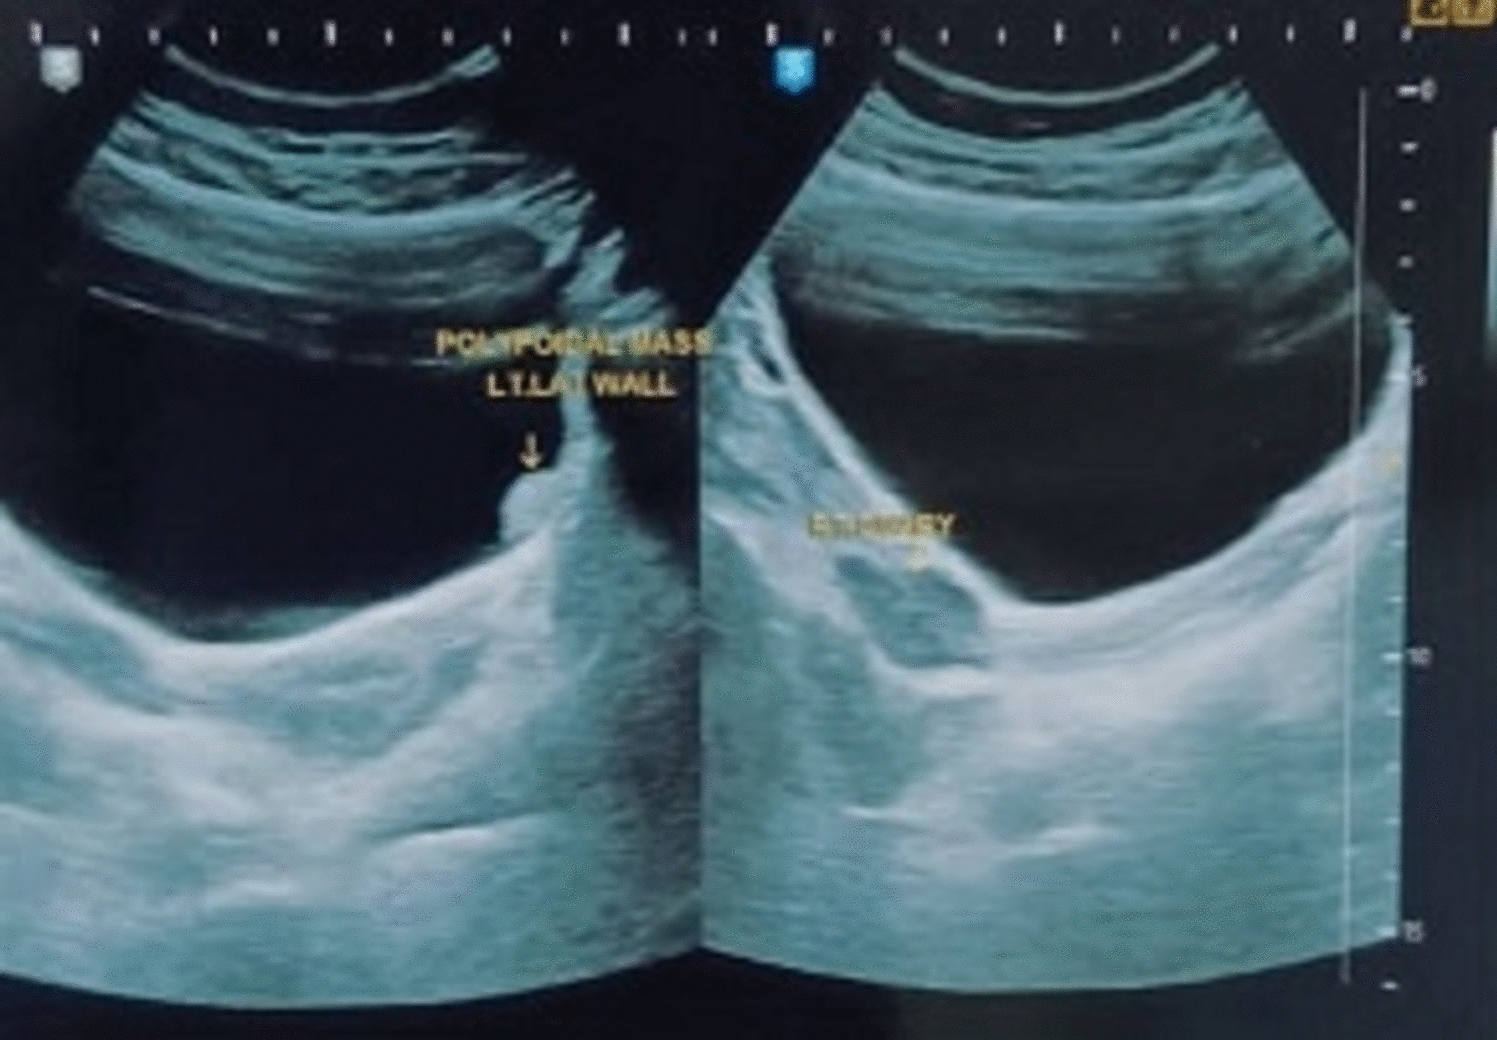

Mean age of the patients was 32.25 ± 6.107 years, and mean BMI was 23.9 ± 3.36 kg/m2. 47.2% had taken medical treatment for a period of 5.9 ± 11.7 months. Regarding parity, 75.4% were nulliparous, and 40.8% patients had infertility as co-existing complaint. According to #ENZIAN, the left ovarian involvement was observed in 67.4% and bilateral involvement noted in 46.1%. A (rectovaginal vagina and septum) was involved in 61% cases, B (uterosacral ligaments and pelvic wall) 63.58% on left and 60.33% on right and C (rectum and sigmoid colon) 33.1% cases.